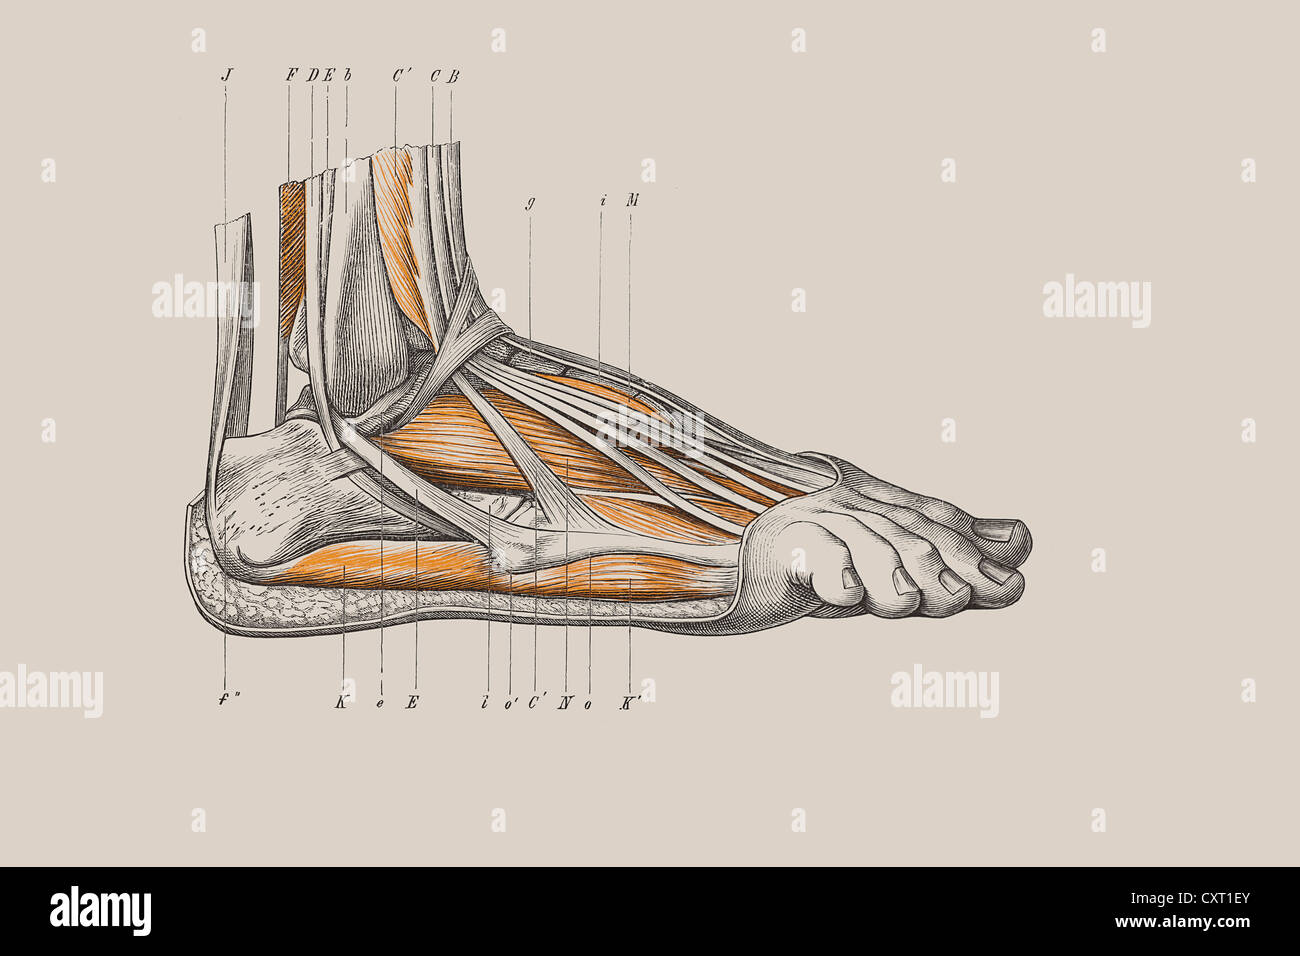

RFPR8GRD–19ème siècle illustration de la jambe gauche de l'avant après avoir enlevé la peau et le fascia. Publié dans Bilder-Atlas Conversations-Le Systematischer zum